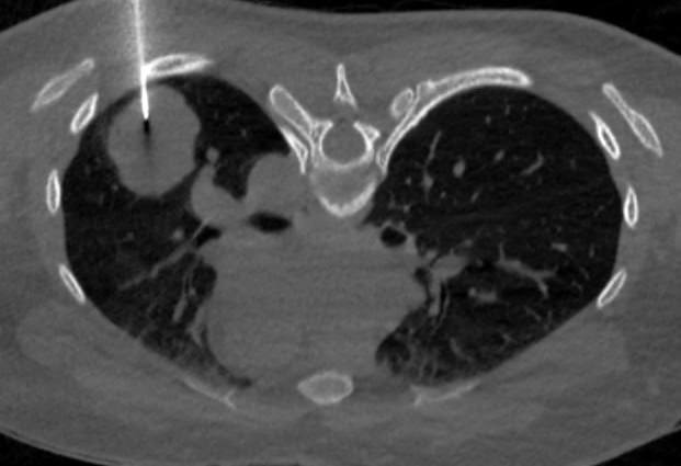

Kết quả xét nghiệm cho thấy Beta-hCG tăng cao tới 1540 U/L, một chỉ số thường chỉ gặp ở phụ nữ mang thai. Chụp CT lồng ngực có tiêm cản quang phát hiện khối u thùy dưới phổi trái, kèm theo nốt nhỏ thùy giữa phổi phải, cần loại trừ tổn thương thứ phát.

Bác sĩ đã chỉ định sinh thiết phổi dưới hướng dẫn CT để xác định bản chất tổn thương. Sau khi phân tích hình thái mô bệnh học, các bác sĩ giải phẫu bệnh đã đưa ra chẩn đoán đây là một loại u ác tính. Tuy nhiên, hình ảnh tế bào rất hiếm gặp và cần phải làm thêm các xét nghiệm chuyên sâu như hóa mô miễn dịch hoặc sinh học phân tử.